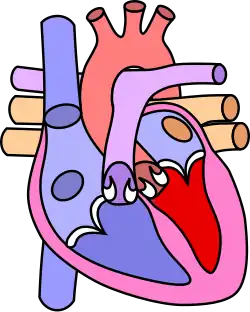

Diagram of a healthy heart and one with tetralogy of Fallot

Normal heart